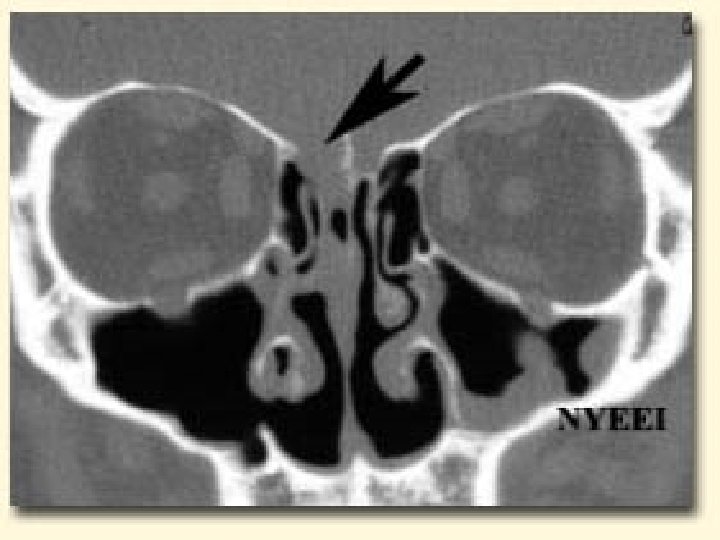

Localization of the leak Radiology plays the key role to see the anatomical site, size, side of the fistula n Bone defects, air fluid levels and erosions can be seen. n Plain X rays… Pneumocephalus/ air fluid levels n CT scan in axial/ coronal views… Skull Base #s, CSF fistulae n MRI… is not used as it is unable to show bone windows n